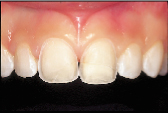

| Figure 3a: A reattachment procedure for the fractured central incisors was done as an interim treatment option. | Figure 3b: Definitive treatment can be delayed until tooth and gingival maturation is complete. |

The corollary to acknowledging the probationary nature of our restorative efforts is that definitive treatment can justifiably be deferred until tooth and gingival

maturation is complete. The fractured central incisors depicted in Figs. 3a and 3b are representative of this principle. The pulps of both teeth were exposed following a traumatic episode. Following pulp capping using the total etch technique, the fractured incisal tooth fragments were reattached by means of a dentin bonding agent.6 Two and a half years later both teeth are vital, but the reattached fragments are discoloured and the patient is dissatisfied with the visible tooth fragment (Fig. 3a). The reattachment procedure was delivered as an interim treatment that not only maintained the biological seal of the pulpal tissues but also allowed for subsequent preparation of veneers (Fig. 3b).